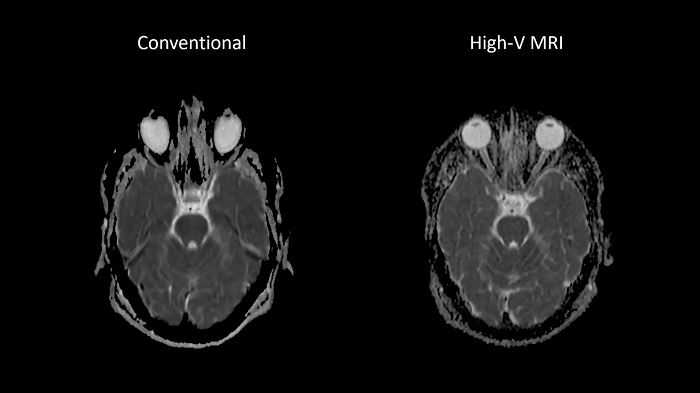

Reduced susceptibility challenges with High-V MRI

In MRI, susceptibility artifacts are a familiar phenomenon.

One notable example of such artifacts is at air-tissue interfaces, as they occur at the sinuses and orbits. The unique field strength of High-V MRI offers physical advantages that reduce susceptibility artifacts. This leads to reduced geometric distortions in diffusion imaging which results in improved diagnostic quality.

Image Courtesy: University Hospital Erlangen, Germany | Image-ID: 1aaaa3439 | 4aaaa0297